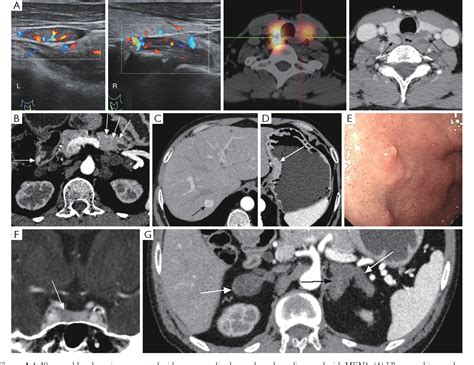

Diagnosing Endocrine Neoplasia Syndromes often involves a combination of biochemical testing and advanced imaging. Since these tumors produce hormones, blood and urine tests that measure hormone levels—such as calcium, parathyroid hormone (PTH), gastrin, or catecholamines—are often the first line of investigation. If these levels are abnormal, imaging modalities such as CT scans, MRIs, or PET scans are utilized to localize the tumors.